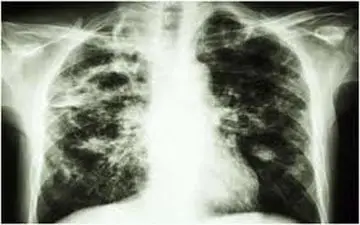

بیماری سل یکی از بیماریهای عفونی و جدی است که اگر به موقع تشخیص داده نشود و درمان نشود، میتواند به عواقب وخیم و حتی…

بیماری سل، یک بیماری عفونی جدی است که در صورت عدم درمان مناسب، می تواند منجر به عوارض خطرناکی مانند نارسایی تنفسی،…

کارشناس مسئول بیماریهای واگیر مرکز بهداشت شهرستان زنجان گفت: سرفه پایدار همراه با خلط، تنگینفس، درد قفسه سینه یا پشت…

میزان بروز سل در ایران ۱۰ برابر کمتر از آمار جهانی است و از هر ۱۰۰ هزار نفر، ۱۴ مورد در معرض ابتلا به این بیماری قرار…